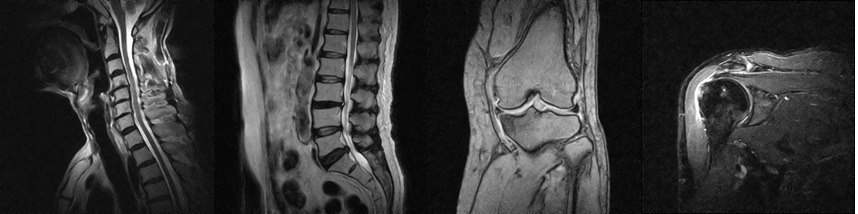

整形外科は、運動器に関わるさまざまな疾患や外傷を対象とする診療科です。運動器とは、骨や関節などの骨格系、それを取り巻く筋肉や靱帯、腱などの支持組織、そしてそれらを支配する神経系を含む身体の仕組みを指します。当科では、これら運動器の機能的改善を重視し、治療に取り組んでいます。

治療対象は、背骨や骨盤といった身体の中心部から、腕や脚などの四肢に至るまで多岐にわたります。当院では以下のような整形外科一般および救急・リハビリテーション医療を提供しています: